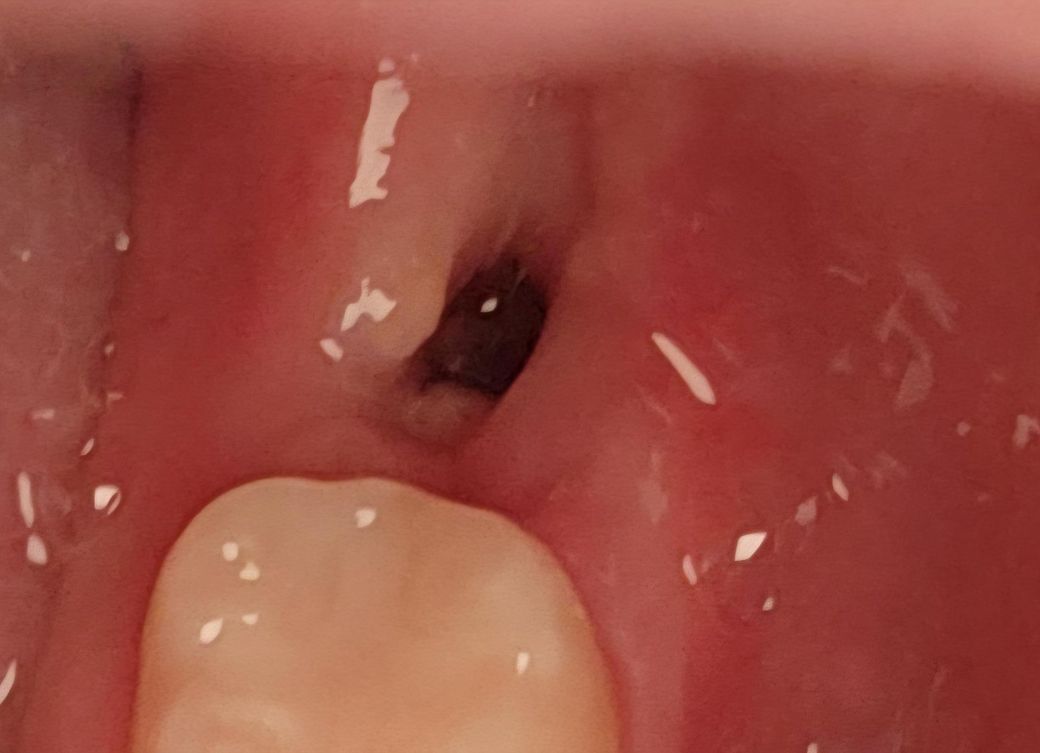

사랑니 발치 5일차 드라이소켓 아닐까요?

저번주 금요일에 빼서 오늘 5일차인데 벌써 혈병이 안보여요 저번에 반대쪽 뺐을 땐 더 오래걸렸는데 이번엔 어제부터 혈병이 거의 안보일 정도로 빠르더라고요 통증은 살짝 욱신거리는 정도만 있고 심한 악취가 난다거나 그런건 아닌데 드라이소켓 가능성은 없을까요? 인터넷에 검색해보니까 저랑 비슷한 사진 보여서 걱정이네요

사진상으로 보면 잘 아물고 있습니다. 아직 잇몸이 다 아문상태가 아니니 음식물이 남아 있지 않도록 관리를 잘해주세요.

발치를 한 부분 내부에는 혈병이 있는 것으로 보입니다. 드라이소켓이 생겼을 경우 강한 통증이 유발되기 때문에 강한 통증이 없다면 드라이소킷이 아닐 가능성이 높습니다.

자세한 확인을 위해서 치과에서 진료를 받아보는 것을 권유드립니다.

사진상으로는 아무문제가 없어보이며 드라이소켓 가능성은 없어보이니 걱정안하셔도 됩니다.

사진상 드라이소켓의 양상 보이지 않습니다 혈병은 원래 발치 후 2일차이후에는 흡수되어 안보이는게 맞습니다